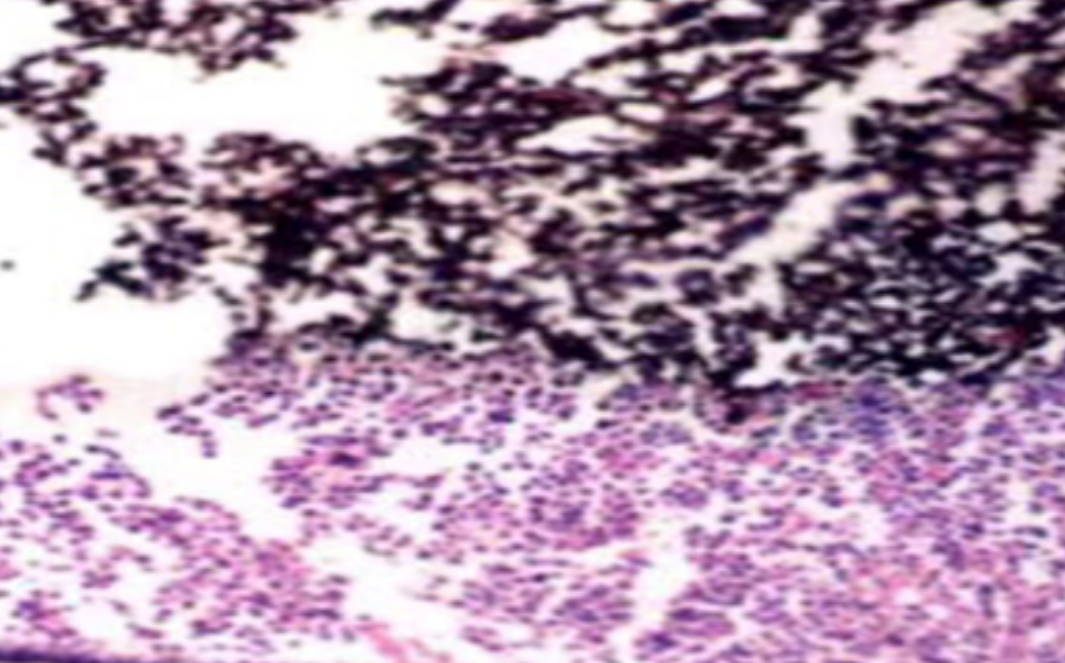

形成原因:切片经梯度乙醇处理后没有完全脱水,导致二甲苯透明、中性树胶封固后残留大量水分。 解决方法:首先移去盖玻片,用二甲苯溶解封固剂如中性树胶,再将切片置入无水乙醇内,待切片重新脱水完全后,用二甲苯透明处理,中性树胶封固。要注意所有用于脱水和透明的液体,在使用一定时间后,应及时更换。 二、细胞核呈红、棕色 形成原因:苏木精染色液过度氧化,切片在苏木精染液染色后返蓝不足。 解决方法:每次染色之前检查苏木精染色液的染色能力,发现苏木精染色液氧化过度应及时更换。此外,切片经苏木精染色后,要给切片以足够的蓝化时间,蓝化过程可用流水、温水、弱碱性溶液(如稀氨水或0.2%碳酸氢钠)等处理。 三、切片在脱蜡后出现大片白色斑点 形成原因:由于烤(烘)片温度太低,切片上的组织蜡膜在脱蜡前没有充分烤(烘)融化。或是因为切片在二甲苯液中停留时间不足,或二甲苯使用过久,造成的脱蜡不彻底。 解决方法:若是由于切片烤(烘)温度低所致,可以先用二甲苯去除切片上的封固胶,然后重新用二甲苯脱去切片上的石蜡,再进行后续染色。若是由于切片在脱蜡的二甲苯中停留时间不足或脱蜡二甲苯使用过久浓度不足所致,则需将切片退回到二甲苯中,停留较长时间,或更换二甲苯液体重新脱蜡,再入乙醇重新脱二甲苯,入0.5%盐酸水溶液褪色后,重新HE染色。 四、细胞核苍白暗淡,即苏木精染色太淡 形成原因:切片在苏木精染色液停留时间太短;苏木精染色液过度氧化,失去染色能力,不能再继续使用;分化步骤处理时间过长;固定不及时。此外值得注意的是,若骨组织细胞核暗淡,大多是脱钙过度造成的。 解决方法:切片重新染色。如果组织在酸性固定液(如Zenker、Bouin)或非中性缓冲甲醛液固定时间过长,细胞核染色能力将减弱,需增加其在苏木精染色液的时间,或用一些方法增加组织的嗜碱性,以改善细胞核的着色。例如,上述组织玻片可以使用Weigert铁苏木精染色液。如果组织是用Zenker液固定的,可将切片脱蜡后放在5%碳酸氢钠溶液3~4h,流水冲洗5min后染色。如果组织是用Bouin液固定的,可将切片脱蜡后放在5%碳酸锂1h,流水冲洗10min后染色。 五、细胞核过染,苏木精染液占据了细胞质 形成原因:玻片在苏木精染色液停留时间过长,或是切片太厚、分化步骤时间太短。 解决方法:如果不是因为切片太厚(用显微镜仔细上下微调,只有一二层细胞核层次),就需将切片进行脱色、漂白、重新染色,适当调整染色和分化时间。但如果确定是由于切片太厚导致的细胞核过染,则需要重新切片。 六、伊红着色淡 形成原因:可能是伊红染液pH值大于5,也可能是蓝化液残留过多,切片太薄,或是切片经伊红染色后在乙醇脱水时间过长。 解决方法:检查伊红染液pH值,必要的话,用乙酸将其调节在4.6~5.0之间,从而使伊红染色色彩艳丽。此外,确保每次蓝化步骤完成后,使用的弱碱性溶液被充分洗去,玻片上没有残留的弱碱性溶液。最后,检查切片的厚度,且脱水时不要让切片在低浓度乙醇中停留时间过长,因为含水多的低浓度乙醇会将切片伊红的颜色分化掉。 七、细胞质过染、分色不足 形成原因:伊红染色液浓度太高,特别是存在焰红燃料、四溴四氯荧光素钠。切片在伊红染色时间过长,或是切片在伊红染色后经乙醇脱水步骤时时间太短,而使乙醇分化伊红的作用不能产生,都能够使细胞质过染。 解决方法:适当稀释伊红染色液,减少伊红染色时间,或使切片在乙醇脱水等步骤时,停留时间相对均匀。同样,也要检查切片的厚度是否合适。 八、切片中出现蓝黑色沉淀物 形成原因:苏木精染色液中的金属膜黏附在玻片上。 解决方法:染色前仔细过滤苏木精染色液,建议使用半氧化苏木精染色液,如Gill苏木精染色液,可以避免过多的金属膜产生。 九、光镜下切片某些区域难以聚焦 形成原因:盖玻片上可能有封固切片的封固剂。 解决方法:移去盖玻片,重新用干净的盖玻片封片。检查切片封片方法,是人工手工封法,还是机器自动封法,如有问题及时调整。 十、封固剂从盖玻片与载玻片之间的缝隙回缩 形成原因:盖玻片弯曲或不平整,或是封固剂含二甲苯过多,稀释过度。 解决方法:移去盖玻片,重新找一张盖玻片,用干净的封固剂封片。如用手工封片法,保证在封固结束时,封固剂容器盖子为紧闭状态。且尽量使用小的容器盛装封固剂,一旦封固剂太黏稠,就可以选择废弃。 十一、细胞核呈灰蓝状态 形成原因:可能由于组织处理温度过高、过热,在液体石蜡中停留的时间过长。或是固定时间太短后,直接在高浓度的乙醇中进行了脱水处理。 解决方法:理论上来说,仅在组织浸蜡步骤才进行加热,组织不能在热蜡液中停留太久。如果由于某些原因不能进行下一步包埋处理,可将组织连同塑料包埋盒一并放置在室温空气中,冷却凝固,以备包埋。待需要包埋时再重新加温直至石蜡融化即可。组织在处理前必须确保固定良好,脱水最好能从低浓度的乙醇开始。 十二、类色素的点状结晶和黑色光滑细胞核 形成原因:这种裸核改变是因为切片封片前放置在空气中的时间太长,以至于二甲苯挥发,切片干燥。 解决方法:移去组织切片上的盖玻片和封固剂,重新处理。将切片水洗数分钟,然后重新脱水、透明、封固。封片过程中要保持组织切片的轻度湿润,尽量不要让其干燥。 十三、染色过淡或过浓 解决方法:如果染色过淡,可以增加染色剂的浓度、延长染色时间或更换新鲜的染色剂;如果染色过浓,则应减少染色剂的浓度或缩短染色时间。 十四、切片出现叠加褶皱 形成原因:新购买的玻片洁净度不够、用镊子撑开切片时操作不够熟练未能平整伸展,或玻片表面有油脂,切片粘贴不牢。另外,烤片时间不足、烤片温度过低或切片过厚造成切片脱落,都会造成重叠或有皱褶的情况。 解决方法:新购买的玻片最好能用硫酸清洁液浸泡一晚,然后流水冲洗干净。在适宜的温度下烤片时间宁长勿短,保证有充足的烤片时间和温度。另外,切片刀要锋利,才能切出厚薄适宜的切片,保证切片不会因为过厚而脱落。 十五、组织残缺不全或有刮划痕迹 形成原因:组织残缺不全是由于切片时修整蜡块时深度不够、组织没有全部暴露于切面。切片的刮划痕迹是由于切片刀的刀锋有缺口、包埋的组织有异物,或是钙化组织、骨组织及包埋石蜡有沙粒造成的。 解决方法:修整蜡块时保证组织块全部暴露于切面,切片时保证切片刀的锋利没刀口。同时在组织取材时去除手术异物和钙化组织。最后,骨组织要完全脱钙,这样可以保证切片的完整和平整美观。 *注:由于实验中导致结果出现误差的原因多种多样,以上内容仅供参考,具体根据实际情况进行判断。